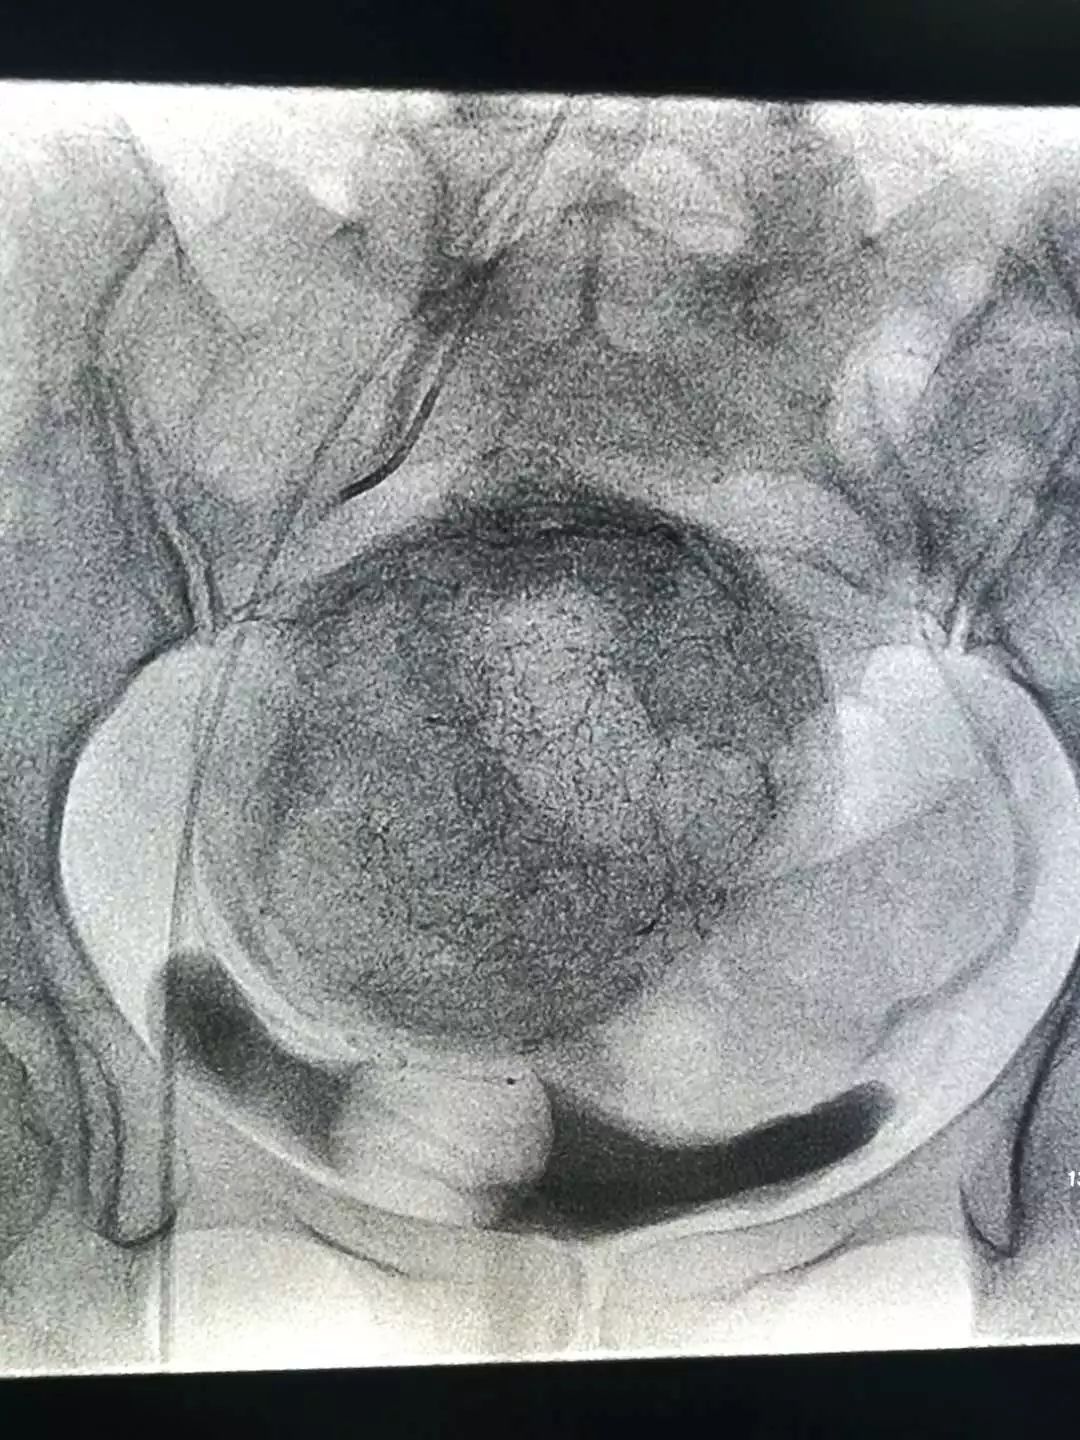

双侧子宫动脉造影,肌瘤以右侧子宫动脉供血为主